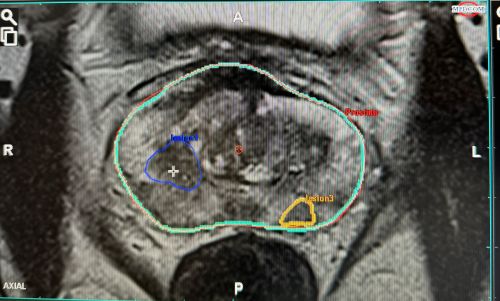

KI - GESTEUERTE FUSIONSBIOPSIE BEI VERDACHT AUF PROSTATAKREBS

Die Fusionsbiopsie bezeichnet das Fusionieren zweier bildgebender Verfahren unter Zunahme der KI-gesteuerten MRT Bilder und eines hochauflösenden Ultraschalls zur gezielten Biopsie (Gewebeprobenentnahme) der Prostata.

Nach der Anfertigung Ihres MRTs lesen wir die gewonnenen Bilder in eine KI-gesteuerte Planungssoftware ein. Hierbei fokussieren wir uns auf die korrekte Kontur Ihrer Prostata, Ihrer Harnröhre und dem Areal, welches von Ihrem Radiologen als Auffällig beschrieben wurde. Diese angefertigte Kontur wird dann in das Ultraschallgerät vor Ihrer Biopsie übertragen. Mit Hilfe dieser Konturen sind wir in der Lage, auch kleinste auffällige Areale gezielt zu biopsieren.

Die großen Nachteile einer transrektalen Biopsie, wie die Möglichkeit einer Enddarmblutung, die Verschleppung von Keimen in die Prostata durch die Darmnähe aber insbesondere die fehlerhafte Biopsieentnahme (falsch-negative-Probenentnahme) wird durch die perineale Biopsie der Prostata bei diesem Verfahren umgangen.

Die modernste Technik der Diagnosefindung bei einem Prostatakarzinom, welche wir in unserer Praxis Wiesloch unter Narkose durchführen, wird aktuell nur von den privaten Krankenversicherungen übernommen oder kann als Eigenleistung des Patienten durchgeführt werden.

Gerne beraten wir Sie in einem persönlichen Gespräch zu diesem Eingriff bei dem Verdacht eines Prostatakarzinoms.